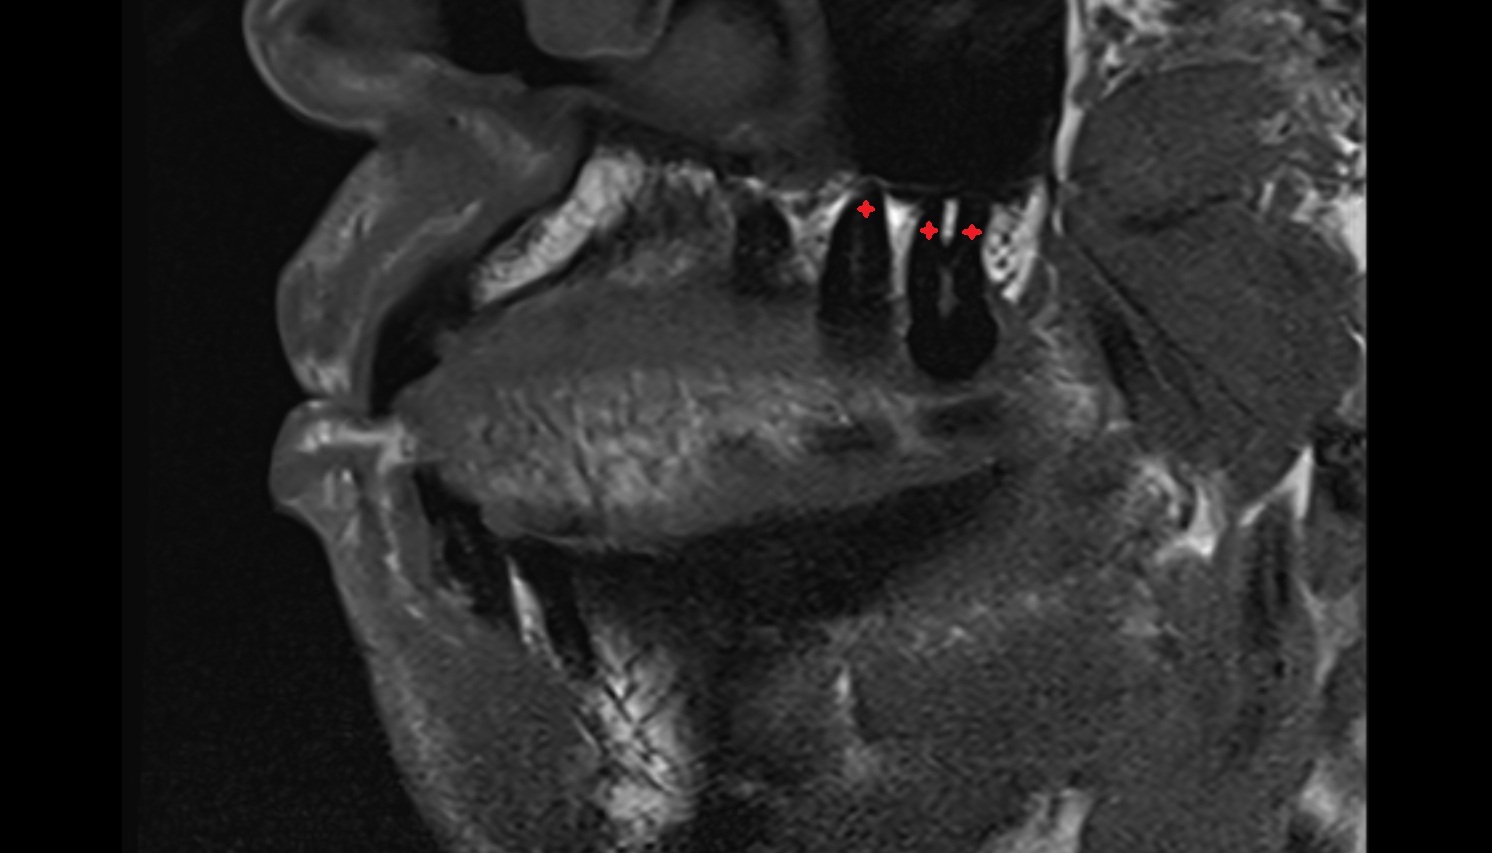

- Articular disc of temporomandibular joint

- Intermediate zone of articular disc

- Temporomandibular joint

- Mandibular condyle

- Mandibular fossa